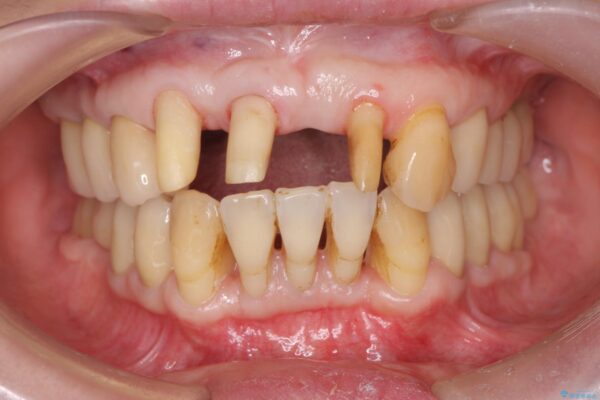

他院でクリーニングのみの歯周病治療を提案され、積極的に自身の歯を残せるような治療を希望され当院に初診来院されました。

歯並び、歯周病の複合的な問題を解決し、長期にわたり安定して維持できるような環境を作り出せるような包括的歯科治療を行っていきます。

まず、保存の難しい歯を抜去したのち矯正治療を行い歯並びの改善、歯周ポケットを除去したことで安定した歯周環境、咬合関係を作り出すことができました。

治療前

歯の総合的なマネージメントを行う包括的歯科治療の実践[ 歯周病・矯正・セラミック補綴 ] 治療前画像 歯の総合的なマネージメントを行う包括的歯科治療の実践[ 歯周病・矯正・セラミック補綴 ] 治療前画像 歯の総合的なマネージメントを行う包括的歯科治療の実践[ 歯周病・矯正・セラミック補綴 ] 治療前画像 歯の総合的なマネージメントを行う包括的歯科治療の実践[ 歯周病・矯正・セラミック補綴 ] 治療前画像 歯の総合的なマネージメントを行う包括的歯科治療の実践[ 歯周病・矯正・セラミック補綴 ] 治療前画像 歯の総合的なマネージメントを行う包括的歯科治療の実践[ 歯周病・矯正・セラミック補綴 ] 治療前画像 歯の総合的なマネージメントを行う包括的歯科治療の実践[ 歯周病・矯正・セラミック補綴 ] 治療前画像